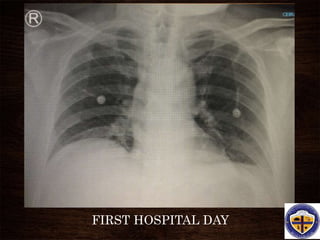

FIRST HOSPITAL DAY

• #41 A representative anteroposterior chest x-ray in the exudative phase of ARDS shows diffuse interstitial and alveolar infiltrates that can be difficult to distinguish from left ventricular failure.